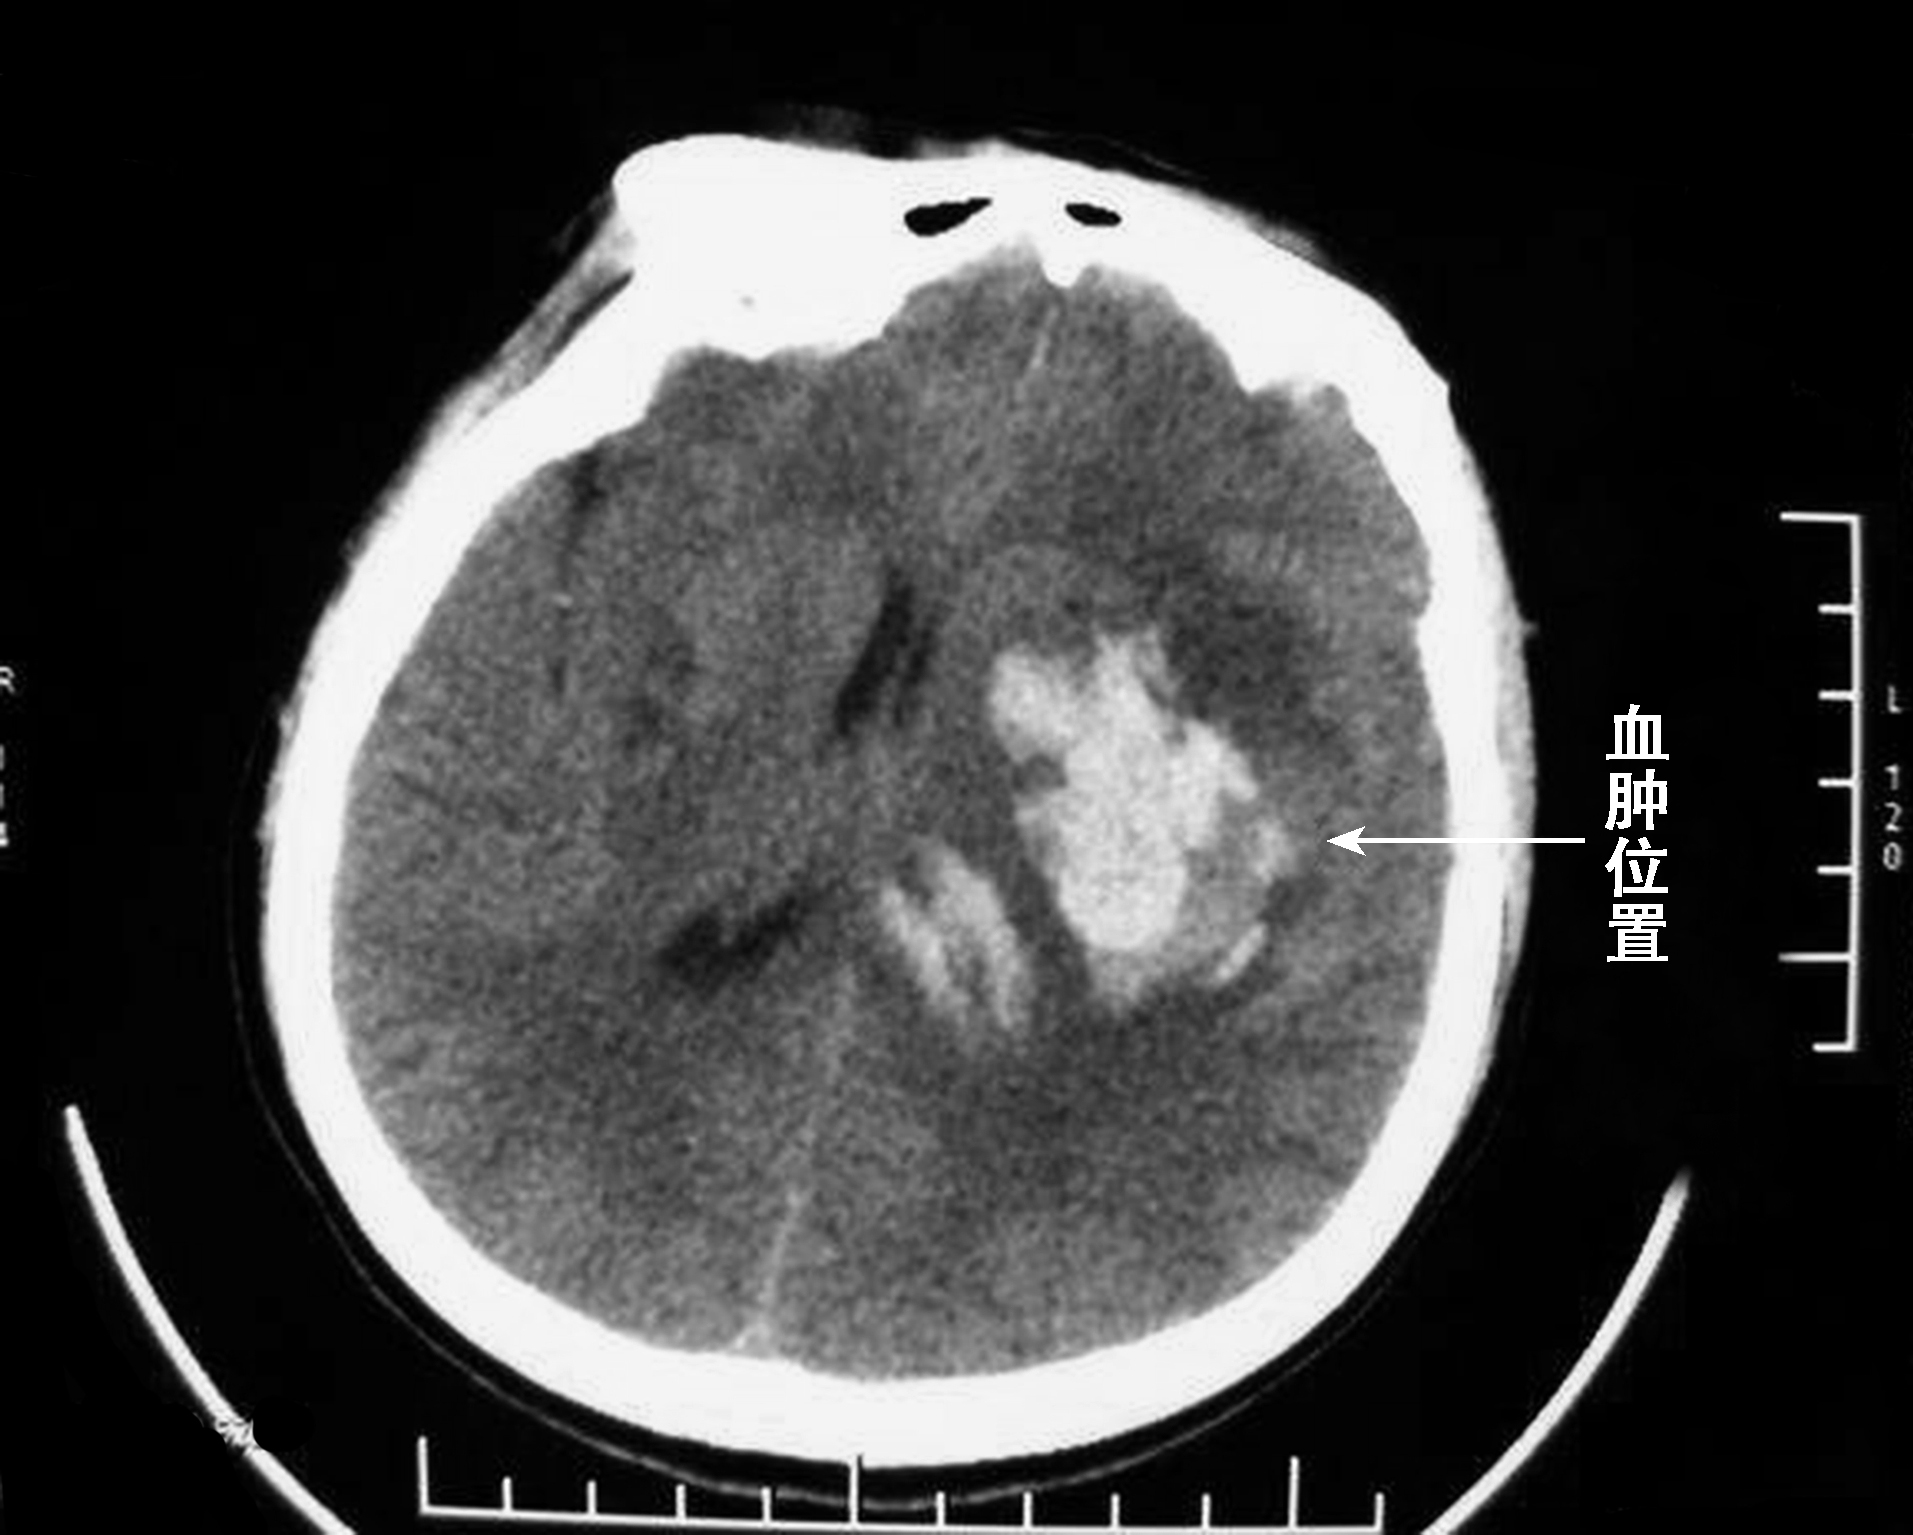

CT检查:脑挫裂伤表现为边界不清的低密度区,血肿为形态不规则的高密度区,血肿较大时,血肿中央部分的密度低于外周的密度,有时还可见中央部分的分层现象,血肿周围有水肿及占位效应。急性期不做增强扫描,慢性期增强扫描周围可见环形强化(图2-4-4)。

图2-4-4 颅内血肿-脑内血肿CT影像表现